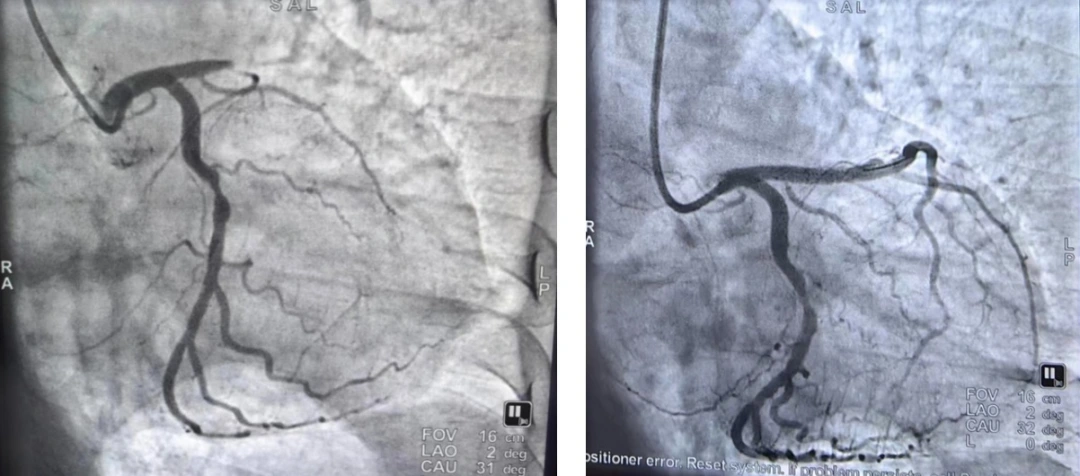

△术前术后影像对比

胸痛中心医生吴凯接诊并完成第一份心电图后,快速做出“急性ST段抬高型心肌梗死”诊断,并马上将心电图和患者基本情况传输至医院胸痛中心救治微信群;心血管内科二病区游三丽主任团队也立即做出回应,建议急诊PCI手术治疗;5分钟内,胸痛中心完成导管室启动、病情及手术告知、护送患者至导管室等一系列救治步骤;患者送达导管室时,心血管内科副主任李贺介入团队已提前到位。通过密切配合,医院胸痛中心团队仅用26分钟就完成了经皮冠状动脉介入治疗,成功挽救了患者的生命。